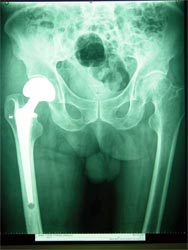

全髋置换术                                单纯股骨头置换术

如果股骨头和髋臼都已经破坏或者预期人工关节要使用很多年,需要进行全髋关节置换术。如果患者为高龄,可以进行单纯股骨头置换术。